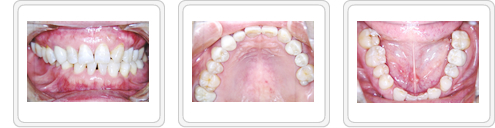

■治療前

左下第1大臼歯の虫歯は神経まで達していました。全体に虫歯が多く存在し、このままでは咬合崩壊の危険性がある状態でした。

■治療後

まず痛みを取り除き、残せる歯は根の治療をし、残せない歯は抜歯という方向で治療しました。

結果的には、左上第2大臼歯のみ抜歯を行い、左上第1、第2小臼歯、左下第1大臼歯、右上第2大臼歯は、白金加金土台装着後、クリセラ冠をかぶせました。

右上犬歯は審美性を考慮し、白金加金土台装着後、ウォルセラム冠をかぶせました。右上第1小臼歯、右下第1大臼歯、左下第2小臼歯、第2大臼歯はクリセラインレーで修復しました。